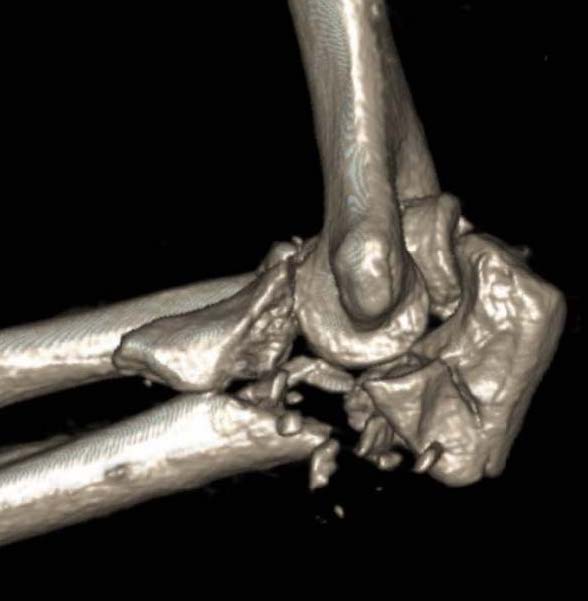

Monteggia variant

Elbow dislocation + olecranon fracture + radial head/neck fracture +/- coronoid fracture

Identify olecranon fracture

- isolate and protect ulna nerve

- dissection out medial and lateral proximal ulna

- reduce and plate olecranon

+/- medial approach for coronoid pocess

- FCU split or elevate entire flexor pronator mass

- identify coronoid process

- small - lasso suture through olecranon

- large - lag screws / buttress plate